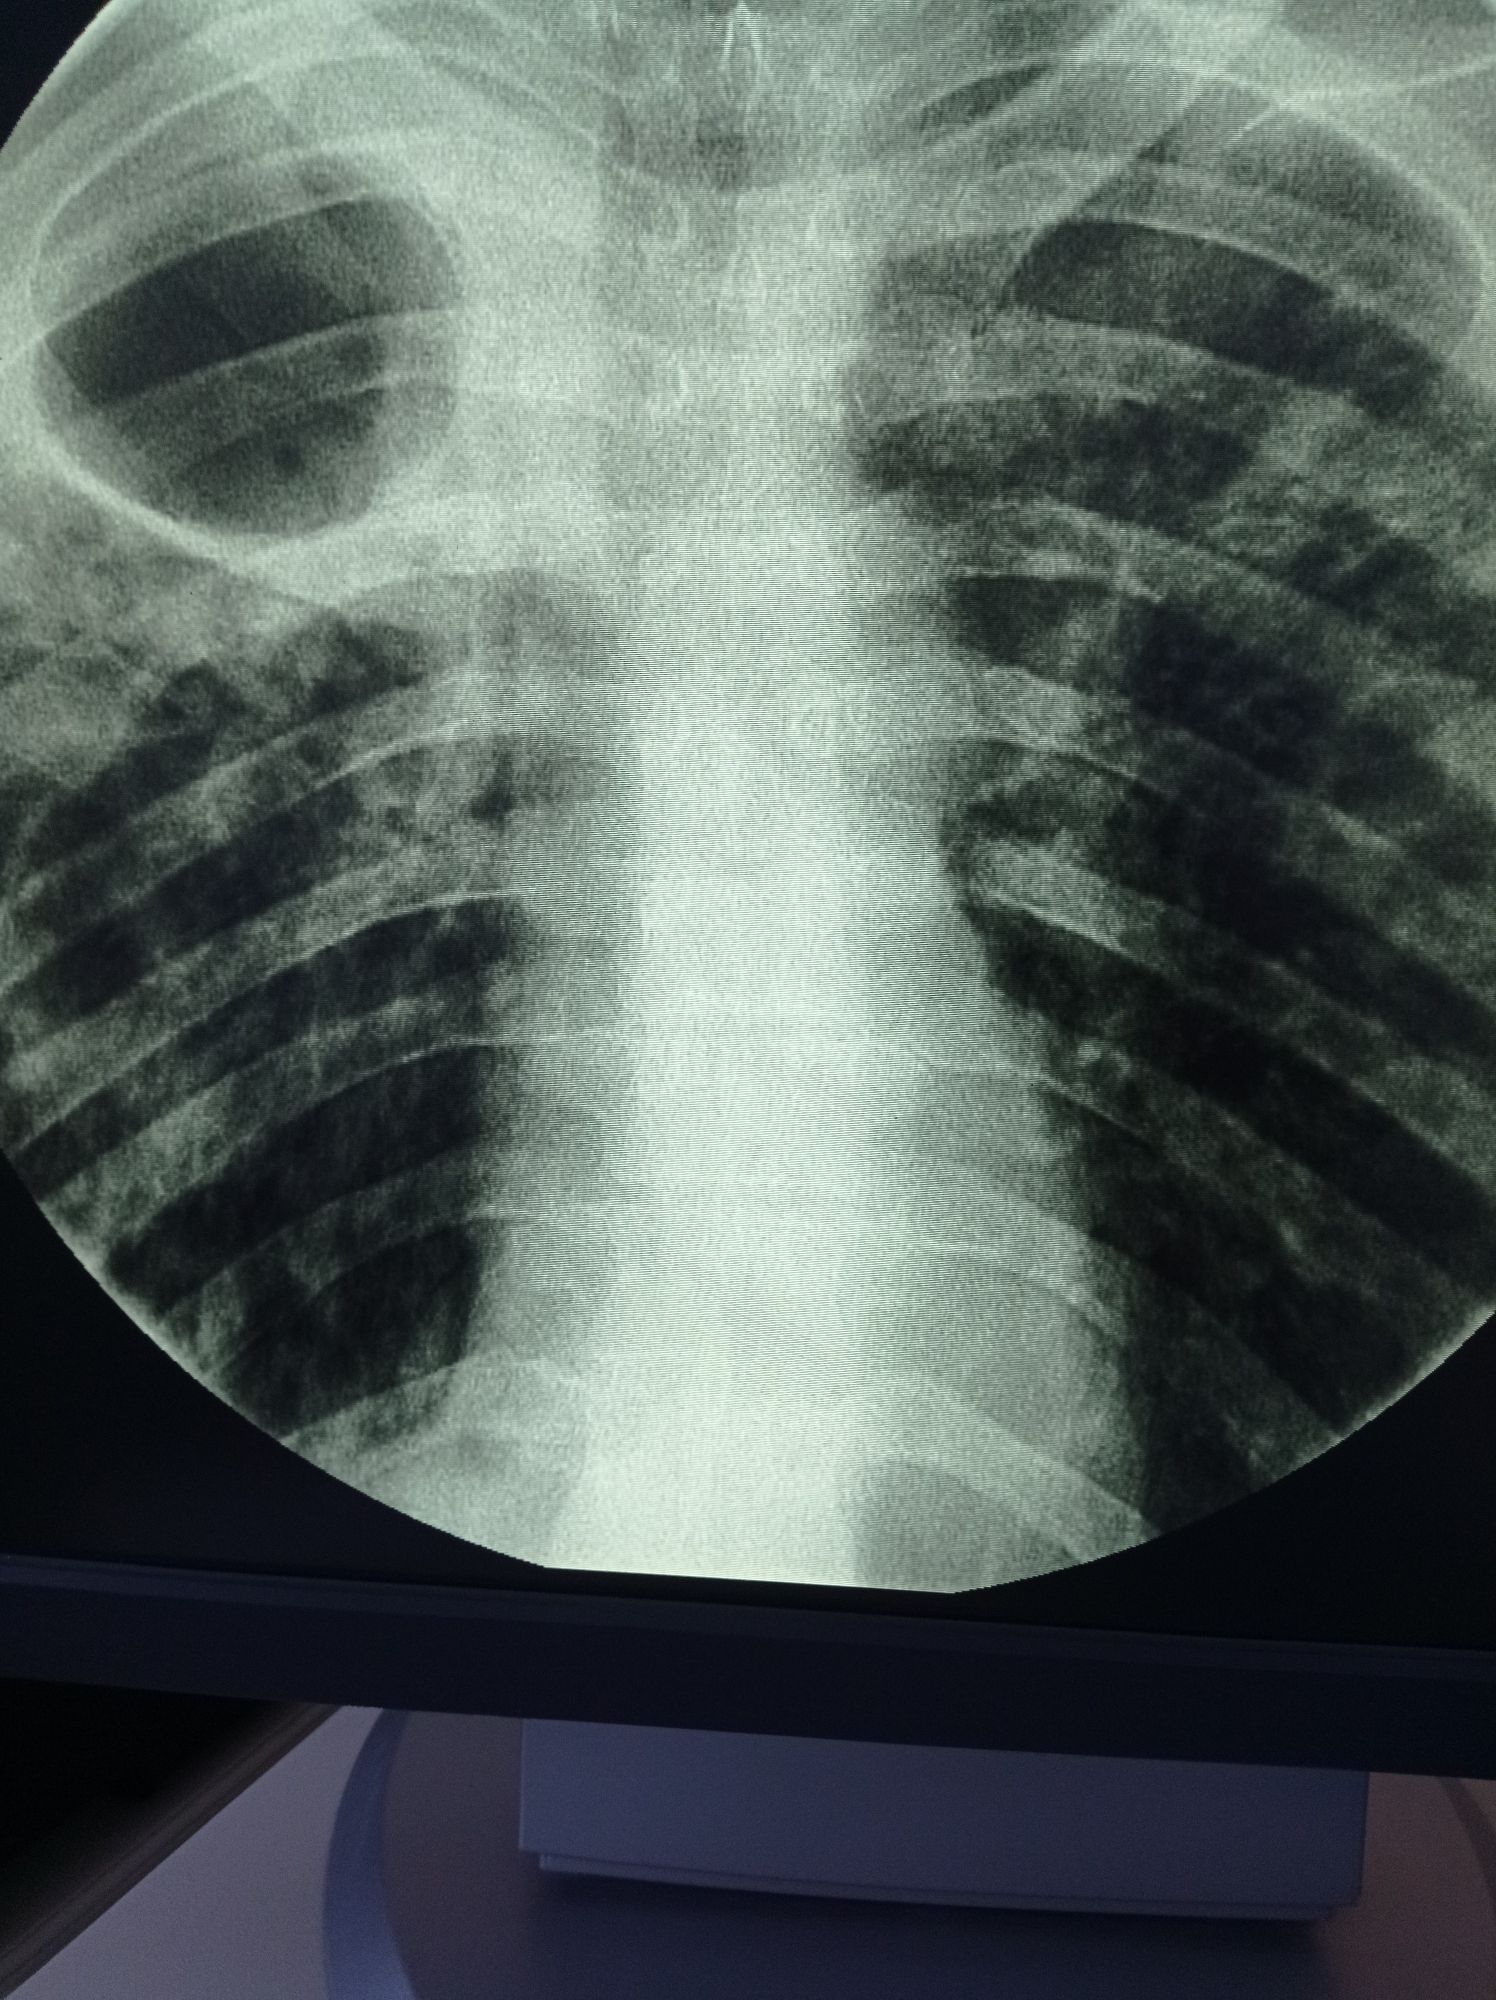

Absses of lung

Xray

Tuberculosis

Cavernoma